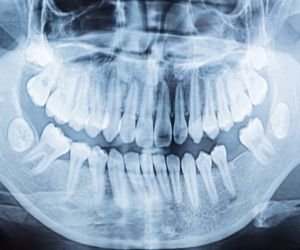

Radiografia dental.